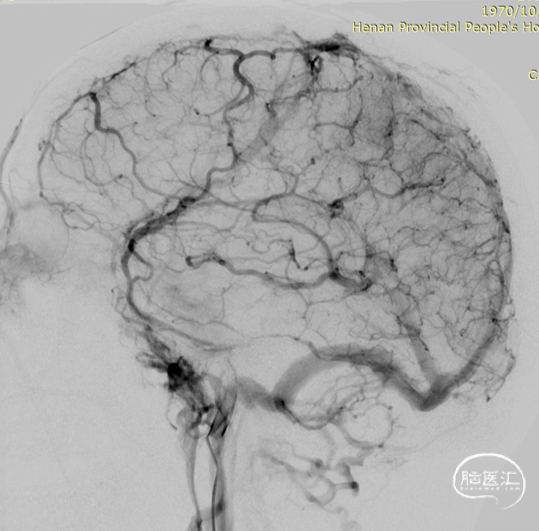

术前DSA静脉期可见上矢状窦及右侧横乙窦充盈缺损。

术前上矢状窦闭塞